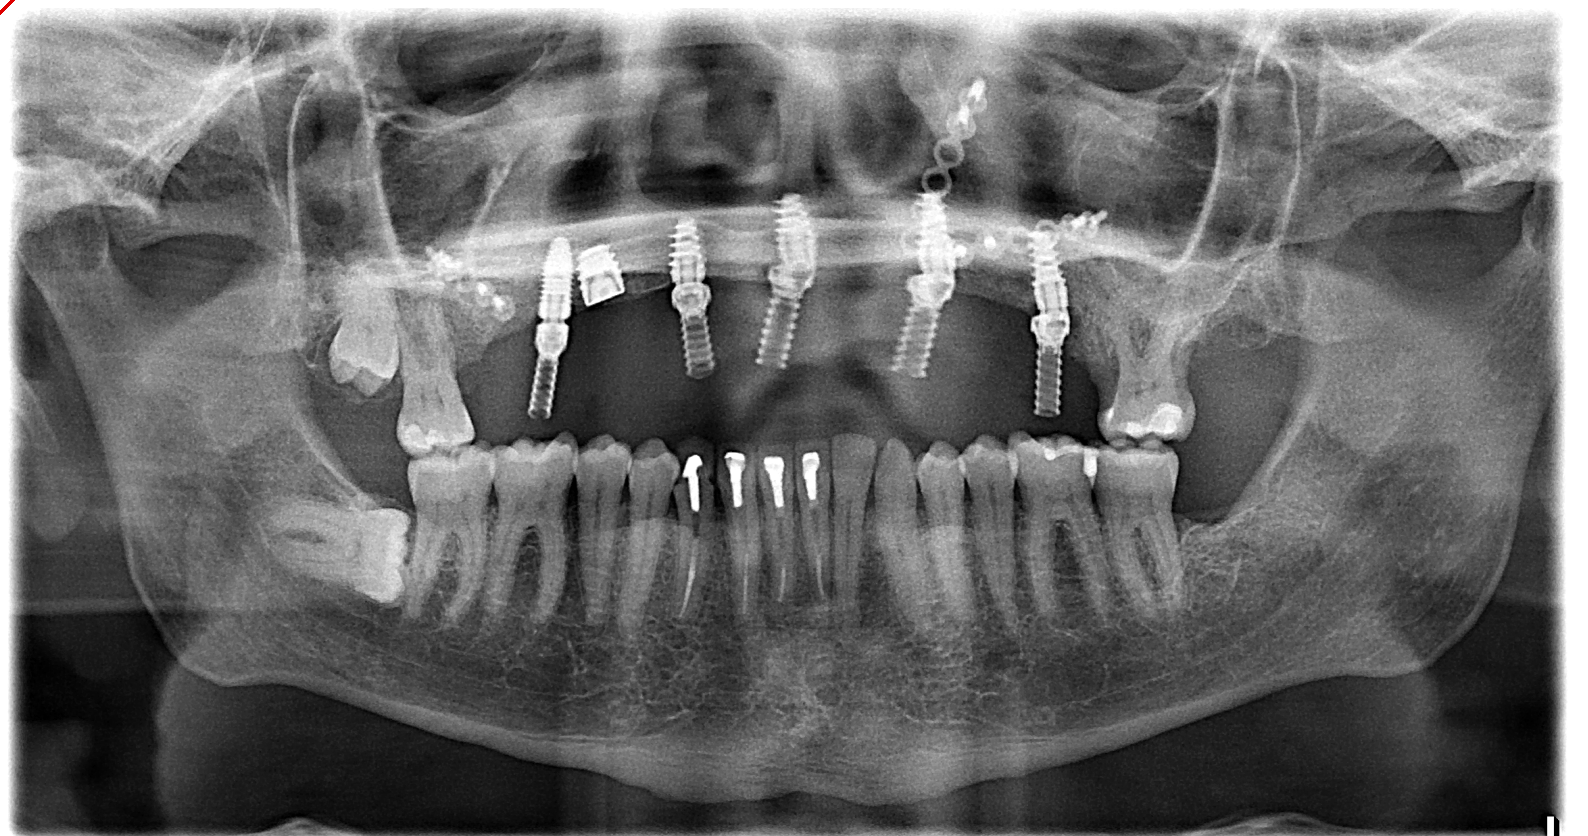

Reconstruction like this is common in Dr. Hussain’s work with veterans recovering from severe facial trauma